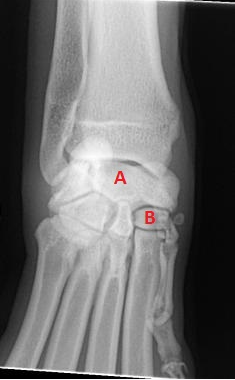

A- radial carpal bone

B- 2nd carpal bone

The most distal joint

Tarsometarsal joint

Central tarsal bone

Red x- fourth tarsal bone

Red arrow- 4th tarsal bone

blue arrow- lateral malleolus, also the origin of the Peroneus longus m. and Lateral digital extensor m.